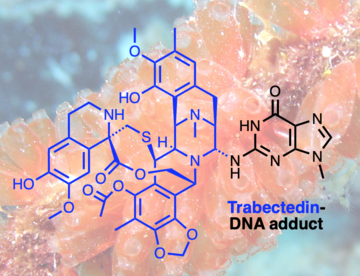

2024-03-13How a Natural Compound from Sea Squirts Combats Cancer

2024-03-13How a Natural Compound from Sea Squirts Combats Cancer